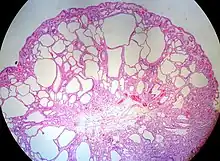

Micrograph of a Peutz–Jeghers colonic polyp – a type of hamartomatous polyp. H&E stain.